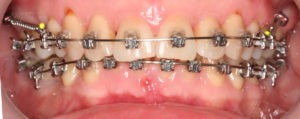

Все этапы ортодонтического лечения и выбор аппаратуры для его осуществления (вид брекет-системы, дополнительные приспособления) согласованы с пациентом.

Искривление окклюзионной кривой (плоскости смыкания зубов), возникшее в результате парадонтита, успешно удалось устранить, используя накусочные брекеты на верхних резцах и микроимплант, установленный во фронтальном участке нижней челюсти: